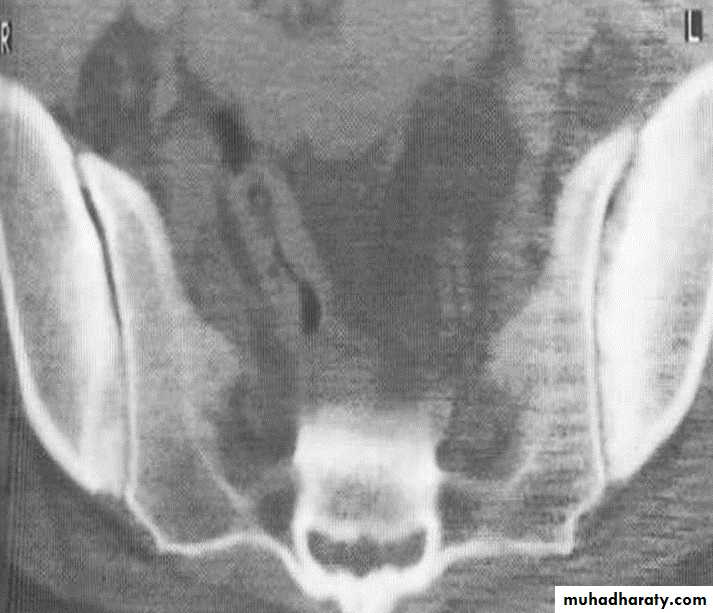

Ankylosing spondylitis-early

(A) Serrated marginsof sacroiliac joints and peri articular sclerosis.

(B) CT scanning demonstrates bilateral sacroiliitis